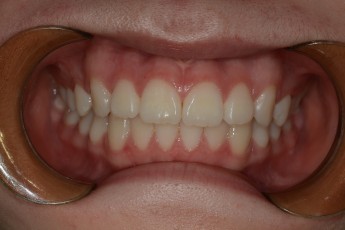

BEFORE & AFTER

- 돌출입교정